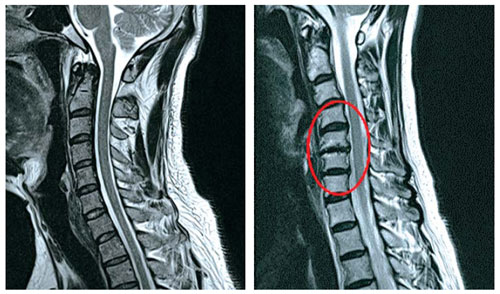

우선 목디스크란 목뼈 사이의 디스크가 손상되어 발생하는 질환을 의미합니다. 디스크는 척추뼈 사이에서 충격을 흡수하고 신경을 보호하는 역할을 하는데, 디스크가 손상되면 신경이 압박되어 통증, 저림, 마비 등의 증상이 나타납니다.

목디스크의 증상은 다양하며 환자마다 그 증상이 다르게 나타날 수 있습니다. 가장 흔한 증상은 목의 통증입니다. 목의 통증은 목 뒤쪽, 어깨, 팔, 손까지 뻗쳐서 나타날 수 있습니다. 또한, 저림, 마비, 감각 이상, 손발의 힘 저하 등의 증상이 나타날 수 있습니다.

하지만 증상이 심하지 않은 경우, 보존적 치료를 통해 호전될 수 있습니다. 보존적 치료에는 휴식, 약물치료, 물리치료, 운동치료 등이 있습니다. 그러나 증상이 심한 경우에는 수술이 필요할 수 있습니다.